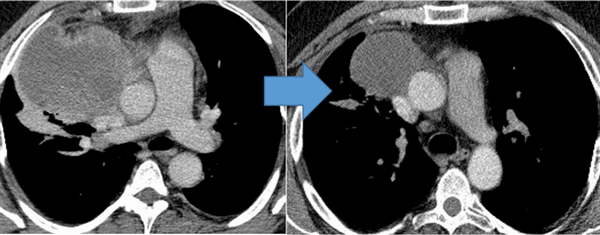

![Герминогенная опухоль средостения до лечения и после 4х циклов химиотерапии по схеме «ВЕР » - уменьшение опухоли более чем на 50% (КТ грудной клетки).]()

Герминогенная опухоль средостения до лечения и после 4х циклов химиотерапии по схеме «ВЕР » — уменьшение опухоли более чем на 50% (КТ грудной клетки)